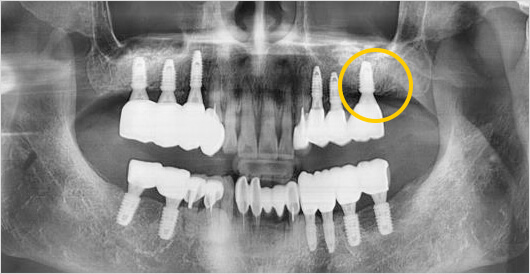

상악동거상술이란 위 턱 어금니 위쪽에 위치한 상악동을 위로 올려준 후 빈공간에 뼈를 이식하여

임플란트를 식립할 공간을 확보하는 고난이도 수술이기 때문에 충분한 시술경험과 노하우가 있는

병원에서 수술 받으셔야 합니다.

고난이도 임플란트 (상악동 거상술) 수술 후